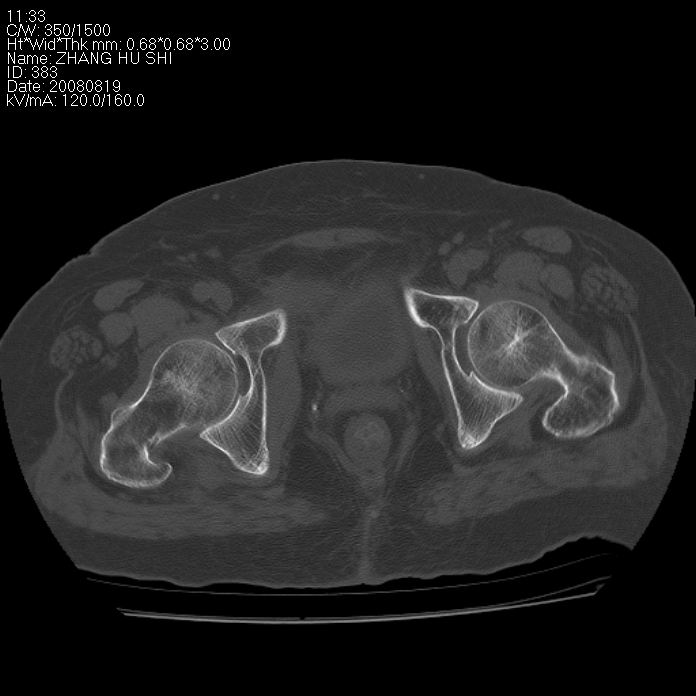

标题: CT15287:女 93岁 右髋关节疼痛 原左侧粗隆间骨折 CT发现右耻 [打印本页]

标题: CT15287:女 93岁 右髋关节疼痛 原左侧粗隆间骨折 CT发现右耻

支持转移并周围软组织侵犯右闭孔内肌侵犯,但tb不能完全除外。

耻骨软骨肉瘤可能性大